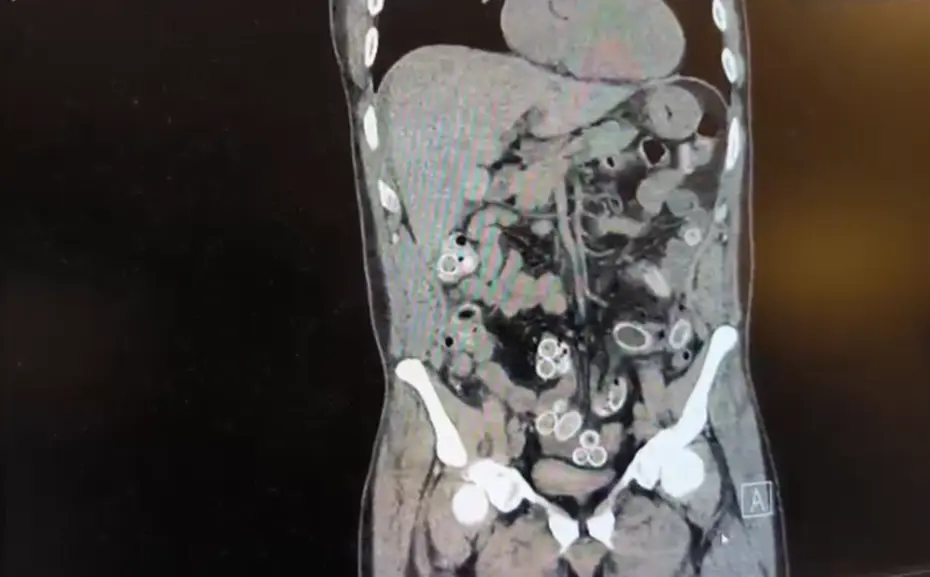

Yapılan muayenenin ardından Cüneyt G.’nin tomografisi çekildi. Şüphelinin mide ve bağırsaklarında yabancı madde tespit edilmesi üzerine hastane yetkilileri durumu polis ekiplerine bildirdi. ESRAR KAPSÜLLERİ AMELİYATLA ÇIKARILDI

Doktorların değerlendirmesi sonrası ameliyata alınan Cüneyt Ç.’nin bağırsaklarından, toplam ağırlığı 259,7 gram olduğu öğrenilen 49 esrar macunu çıkarıldı.